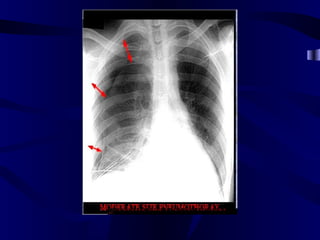

Paratracheal and Hilar Lymphadenopathy: ?Diagnosis

NORMAL

Sarcoidosis

Paratracheal and HilarLymphadenopathy: ?Diagnosis